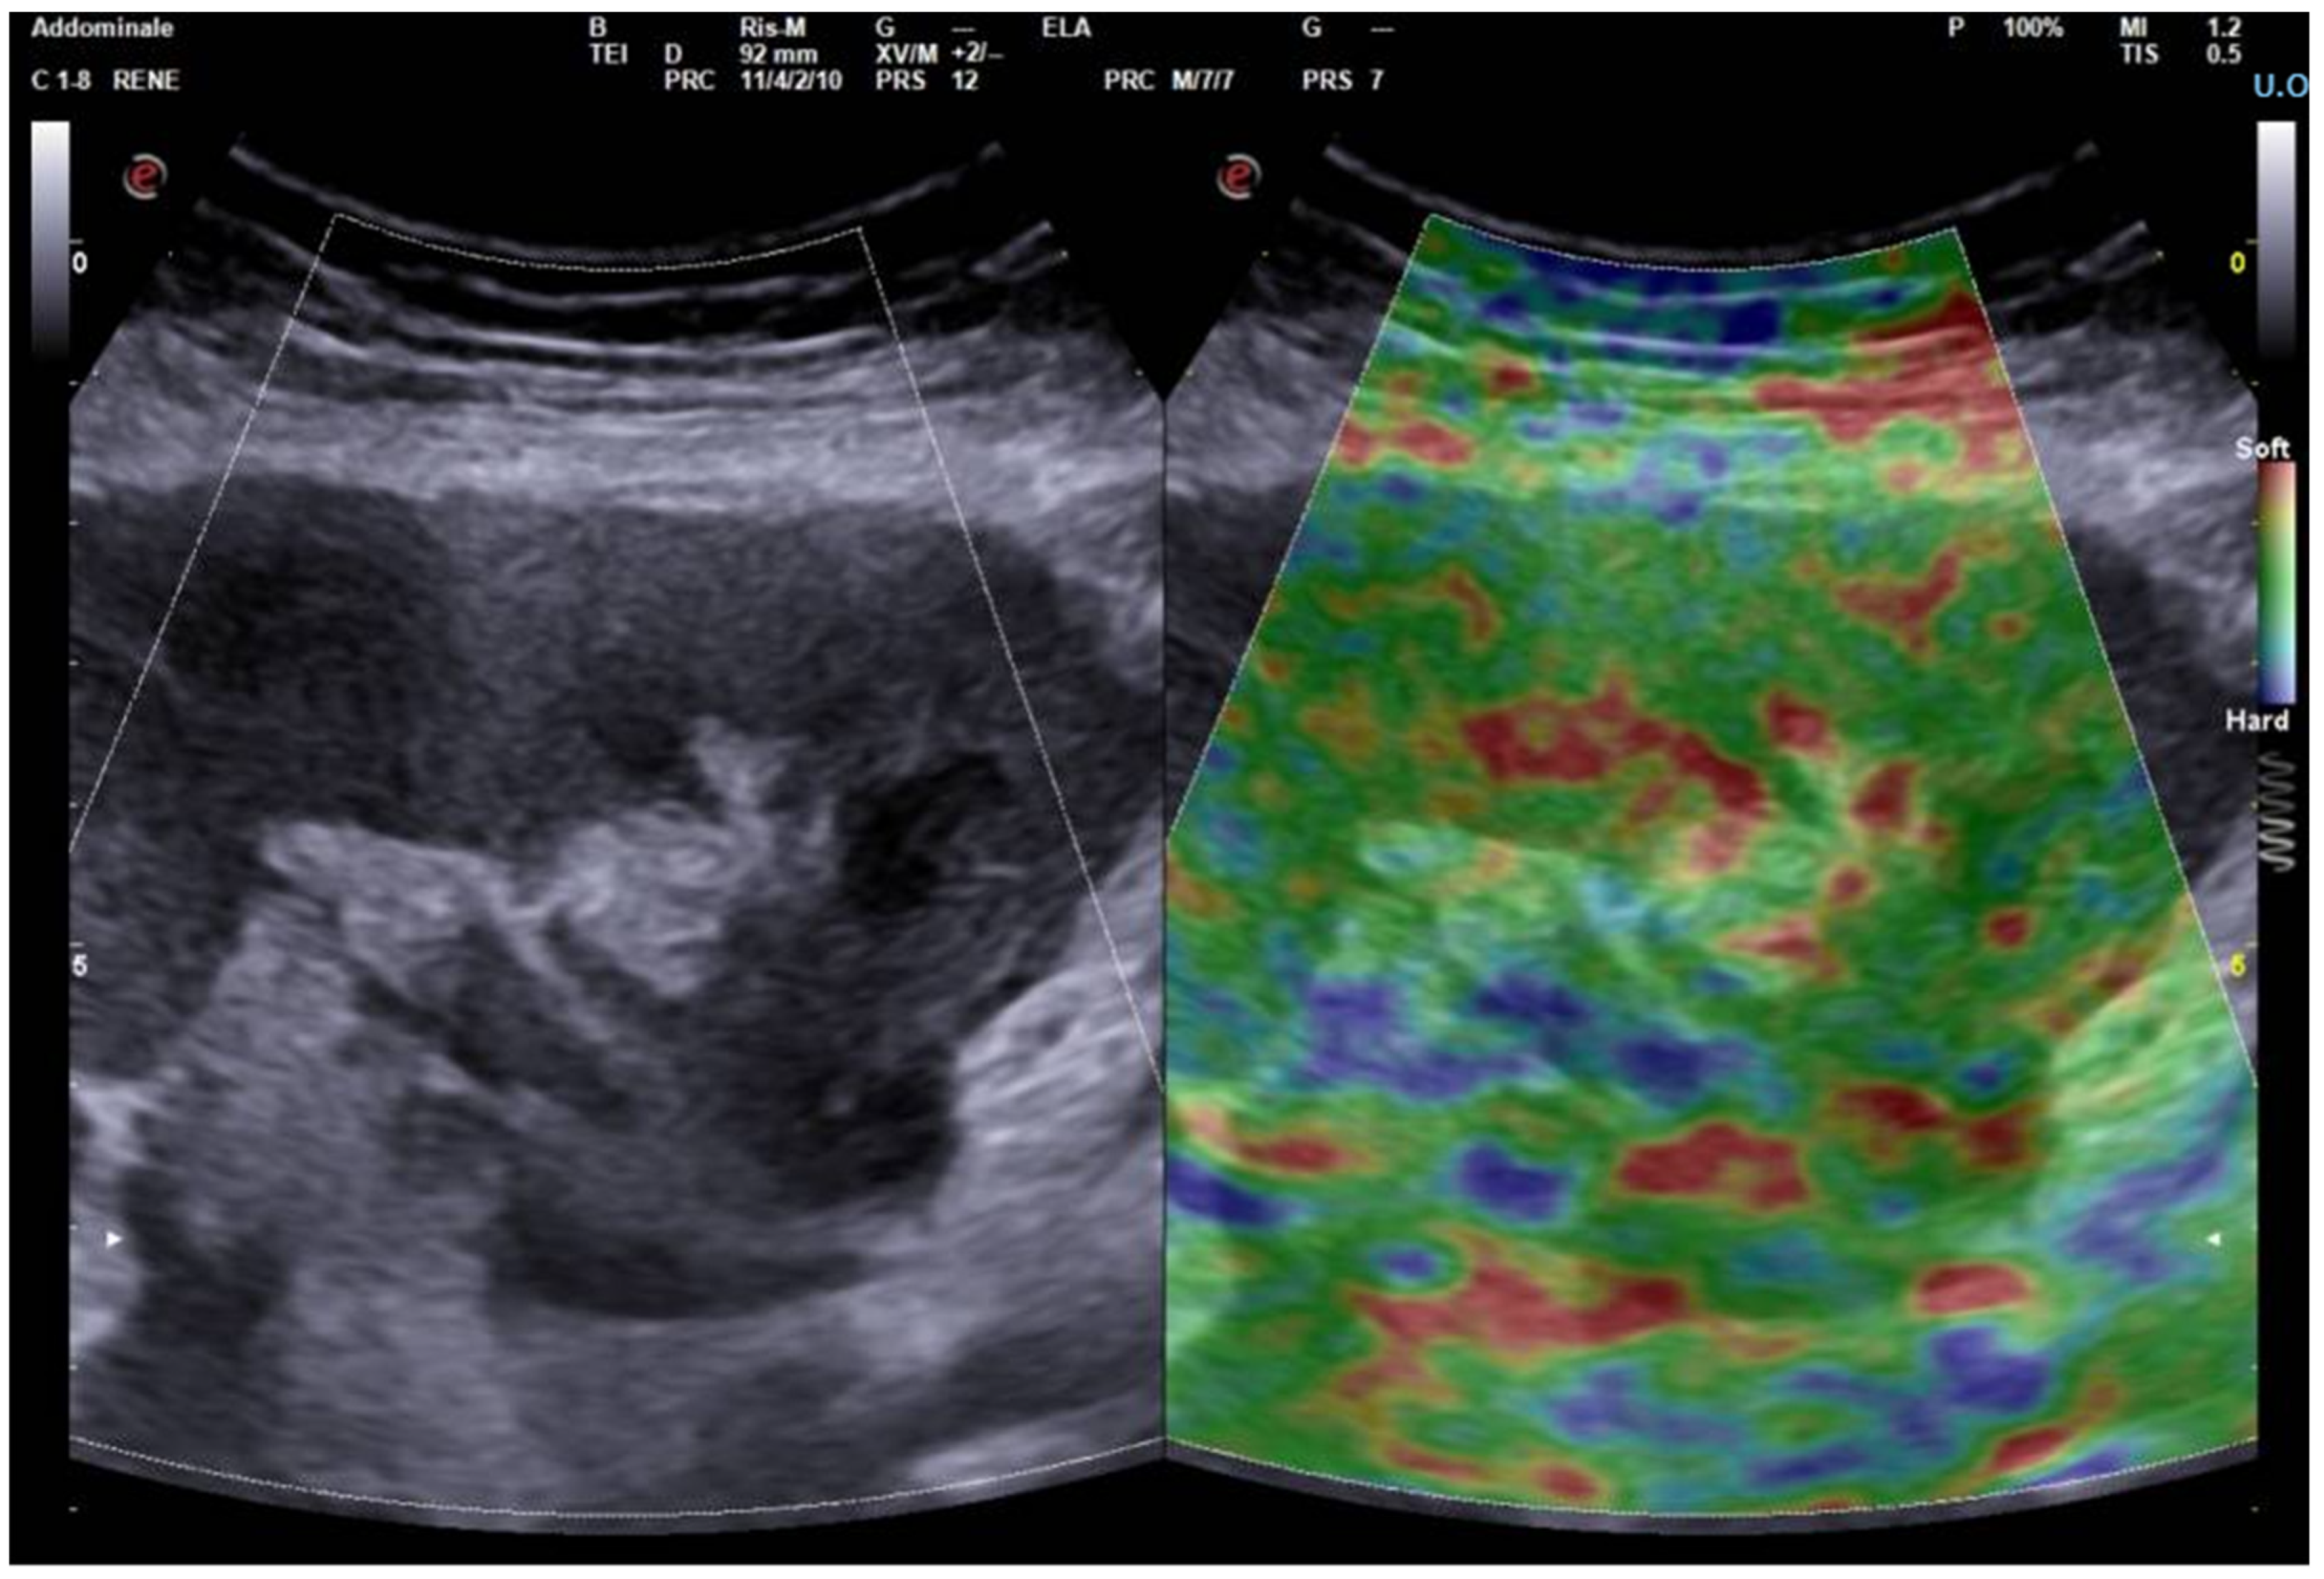

2. Principles of Operation and Comparison of Techniques

3. Elastography in the Kidney: Basic Technique and Limiting Factors